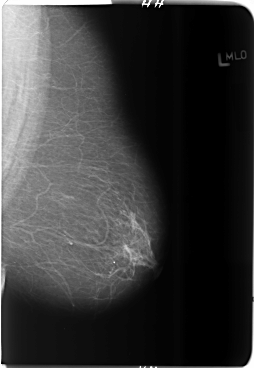

B_3685_1.LEFT_MLO

LEFT_MLO LINES 5880 PIXELS_PER_LINE 4064 BITS_PER_PIXEL 12 RESOLUTION 50 NON_OVERLAY